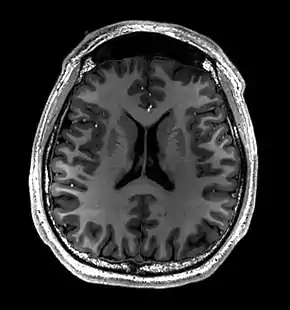

Brain regions on T1 MRI

MRI image of the surface of the brain.

- T1-weighted (T1W) images: Cerebrospinal fluid is dark. T1-weighted images are useful for visualizing normal anatomy.